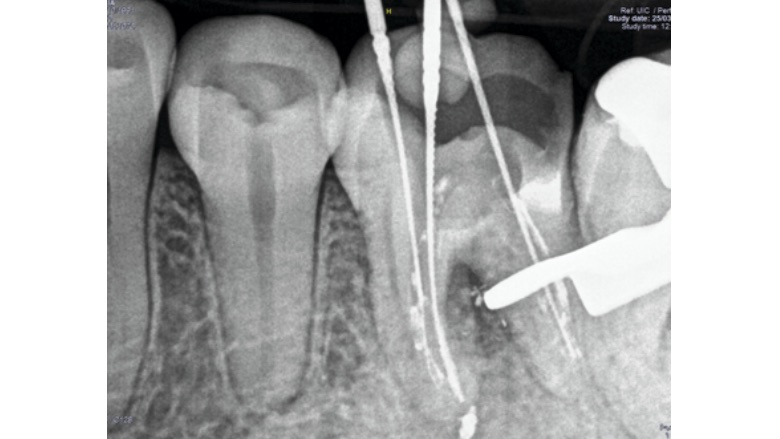

Fig. 6. Remoción de la gutapercha y localización de la longitud de trabajo.

La remoción de la gutapercha se llevó a cabo con instrumentación rotatoria complementando la conformación de conducto con un sistema reciprocante.